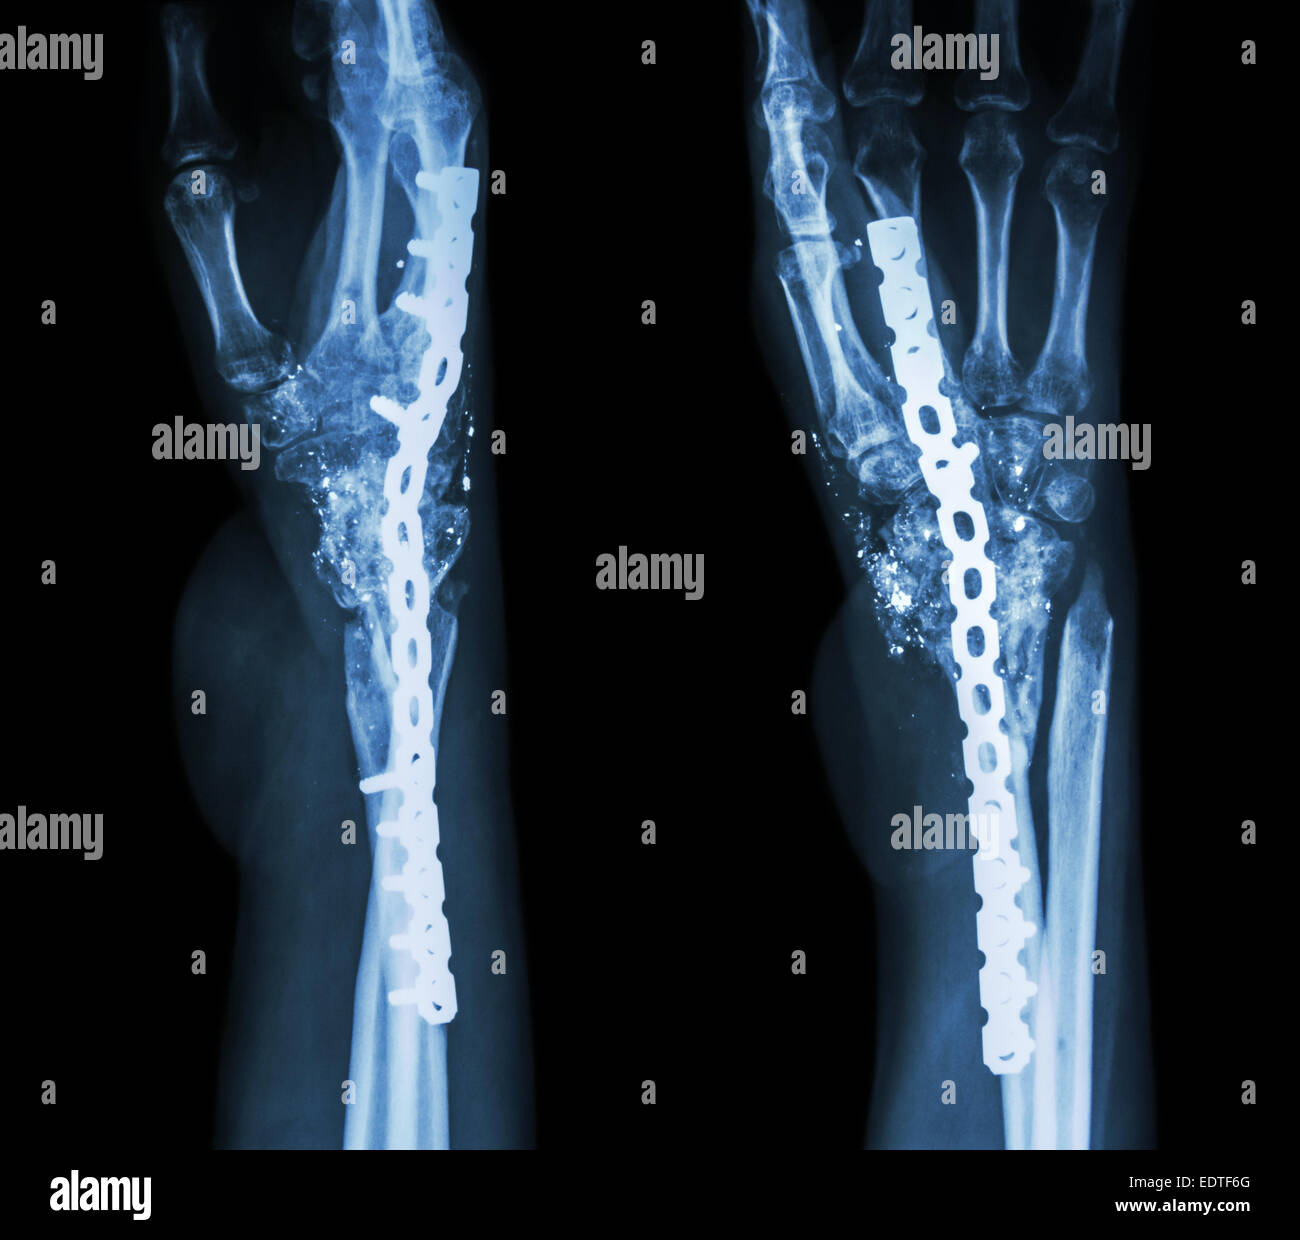

From www.alamy.com

Wrist xray showing a fractured distal radius and ulna Stock Photo Alamy Compression Fracture Wrist most wrist fractures and dislocations are a result of axial loading on the outstretched palm and extended wrist, usually from a fall on. when the radius breaks near the wrist, it is called a distal radius fracture. distal radius fractures (broken wrist) a fracture of the distal radius occurs when the radius — one of the two. Compression Fracture Wrist.

Wrist fracture hires stock photography and images Alamy Compression Fracture Wrist wrist fractures affecting the distal radius are the most common fracture in adults and children and are typically. The break usually happens due to falling on an outstretched or flexed hand. Distal radius fractures are the most common orthopaedic injury and generally result from fall on an outstretched hand. most wrist fractures and dislocations are a result of. Compression Fracture Wrist.